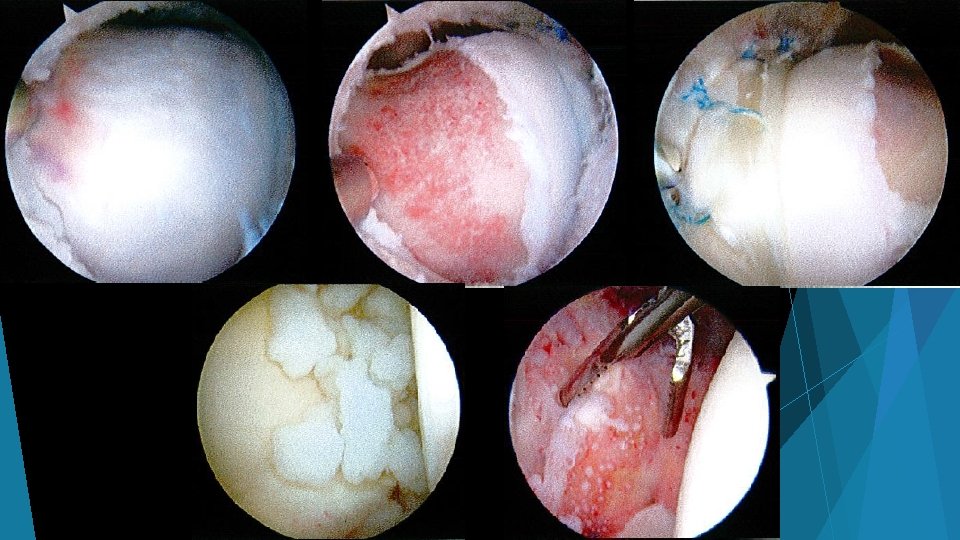

Shear forces on cartilage at chondrolabral junction Impingement with hip flexion Subtle findings on MRI: marcaine arthrogram with traction, 1. 5+ T MRI